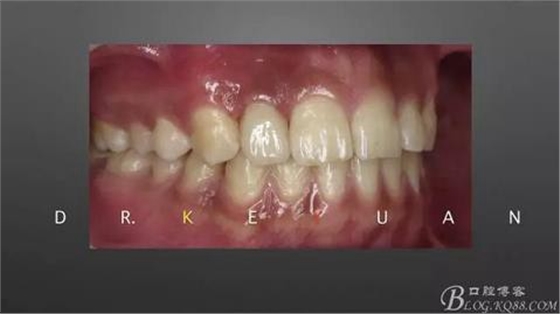

10、復(fù)診試戴最終修復(fù)體(又爭取了2周的時(shí)間,再加上技師對(duì)最終修復(fù)體鄰接關(guān)系的設(shè)計(jì),牙齦恢復(fù)效果明顯)

11、牙齦狀況對(duì)比(有時(shí)候你把患者約的時(shí)間太長,他可能會(huì)不理解你,約著約著就再也約不過來了,有些時(shí)候患者的修復(fù)熱情和臨床的治療程序可能成反比,我們要做金玉其外、金玉其中的修復(fù),實(shí)難取舍)

12、粘接后即刻(齦緣的高度略有差異,這應(yīng)該可以說明冠延長術(shù)和正畸牽引的效果差異)